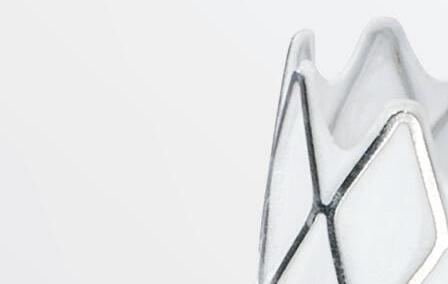

Paul J. Foley III, MD, a vascular surgeon and director of the non-invasive vascular lab at Doylestown Hospital in Doylestown, Pennsylvania, and adjunct associate professor of surgery at the University of Pennsylvania in Philadelphia, discusses the virtues of the new Shockwave E8 IVL catheter.

Endovascular interventions for chronic limb-threatening ischemia (CLTI) are technically demanding endeavors. Multi-level arterial disease, long-length lesions and other complex plaque characteristics are frequently encountered when treating these patients.1,2 Calcium modification with intravascular lithotripsy (IVL) has emerged as a useful tool to combat the challenges of calcified lesions with the goal of maximizing luminal gain to achieve improved endovascular outcomes, both radiographically and clinically.3 Balanced lithotripsy pulse delivery across longer-length lesions, as well as effectively treating calcified disease across multiple arterial beds, can be laborious considering the number of available pulses and the length of the IVL catheter relative to the extent of disease.

To address this, the Shockwave IVL peripheral portfolio has now been enhanced with the addition of the Shockwave E8 catheter. The Shockwave E8 contains eight emitters across an 80mm-length balloon platform with treatment diameters ranging from 2.5–6mm and the ability to deliver up to 400 pulses. A working length of 150cm now provides an extended reach for more distal disease. The Shockwave E8 catheter allows for expanded application of IVL in treating a wide range of infrainguinal disease. Longer-length lesions involving the superficial femoral (SFA) and popliteal arteries or disease involving multiple tibial arteries that may have previously required a very selective pulse delivery approach can now be more broadly treated with the Shockwave E8.